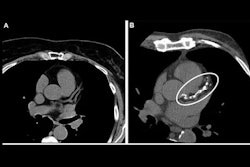

Calcium scores are derived from chest CT scans and are based on the amounts of calcium deposits in the coronary arteries. These deposits are associated with atherosclerosis and increase the risk of heart attack and stroke. Thus, CAC scores are recommended in clinical guidelines to establish risk in individuals for coronary artery disease.